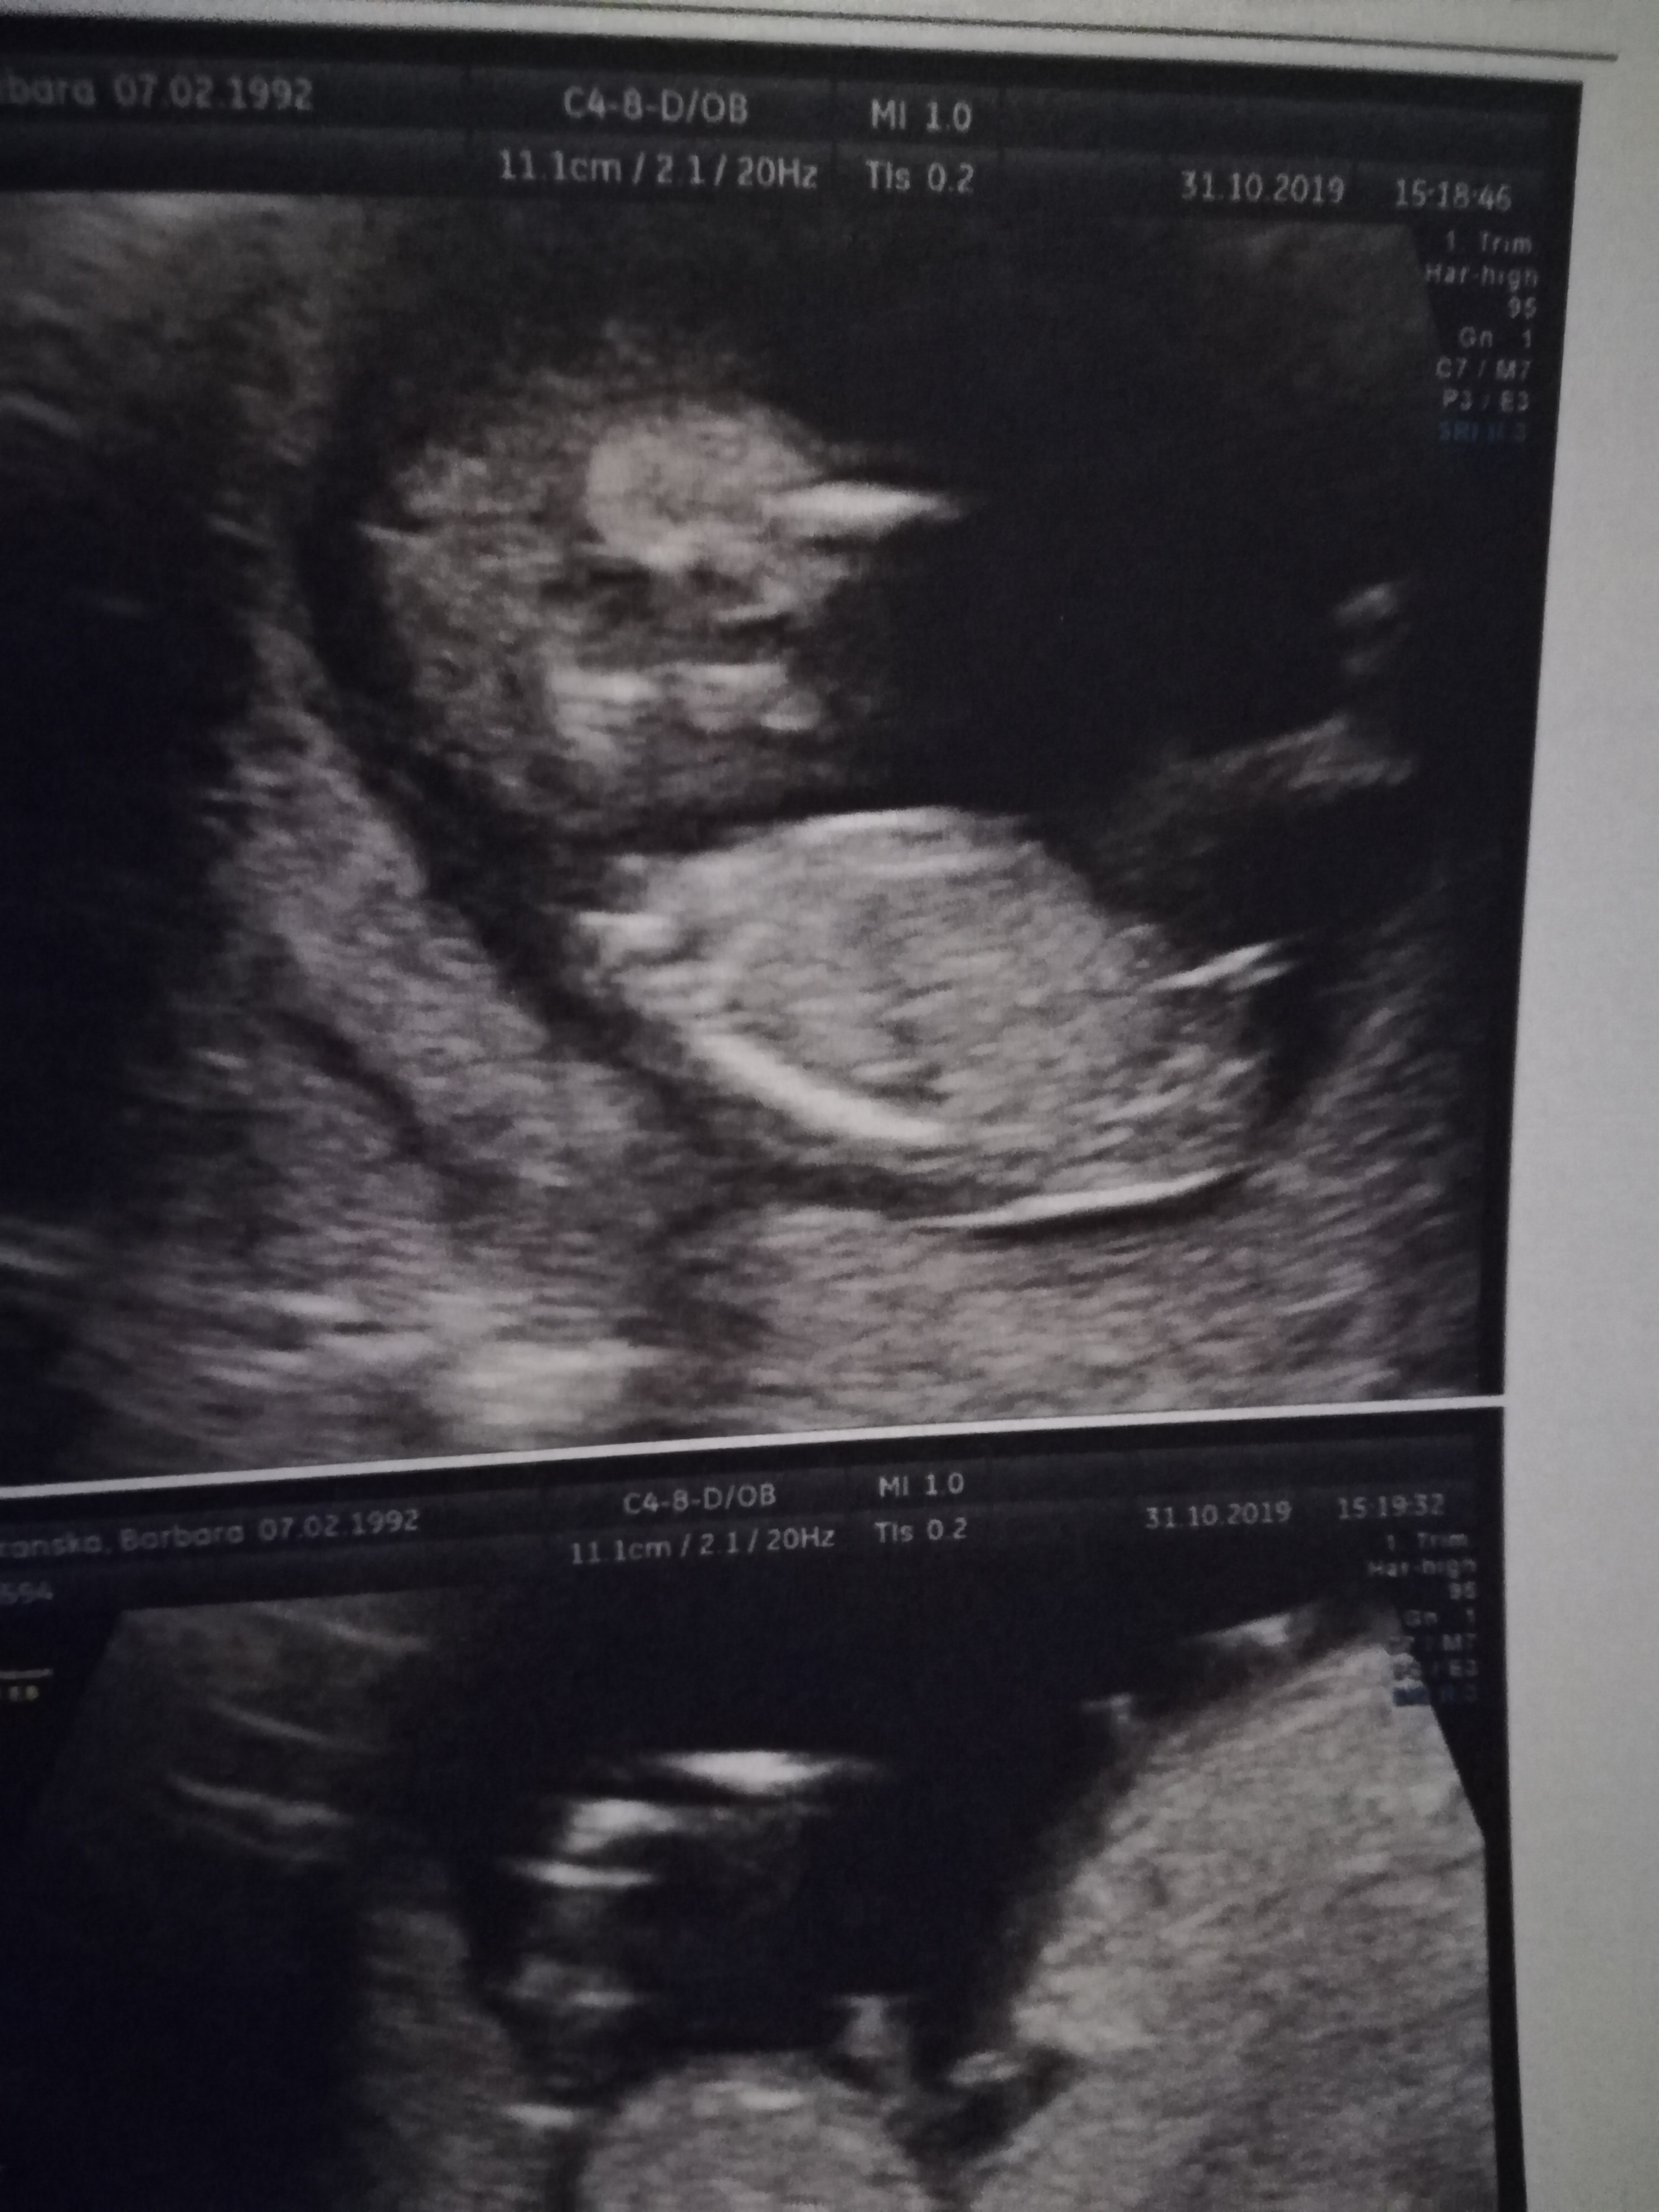

Usg chłopak czy dziewczynka?

Witajcie mam pytanie odnośnie usg nie ukrywam że liczę na dziewczynkę ale najważniejsze żeby zdrowe było. Lekarz jakiś tępy i nic nie powiedział o tym a ja oszaleje. Chodzi o te usg u góry dziękuję za odpowiedź

Mamusiowelove - niby wygląda mi na dziewczynkę, ale lepiej, żeby to lekarz stwierdził, bo ma większe doświadczenie...